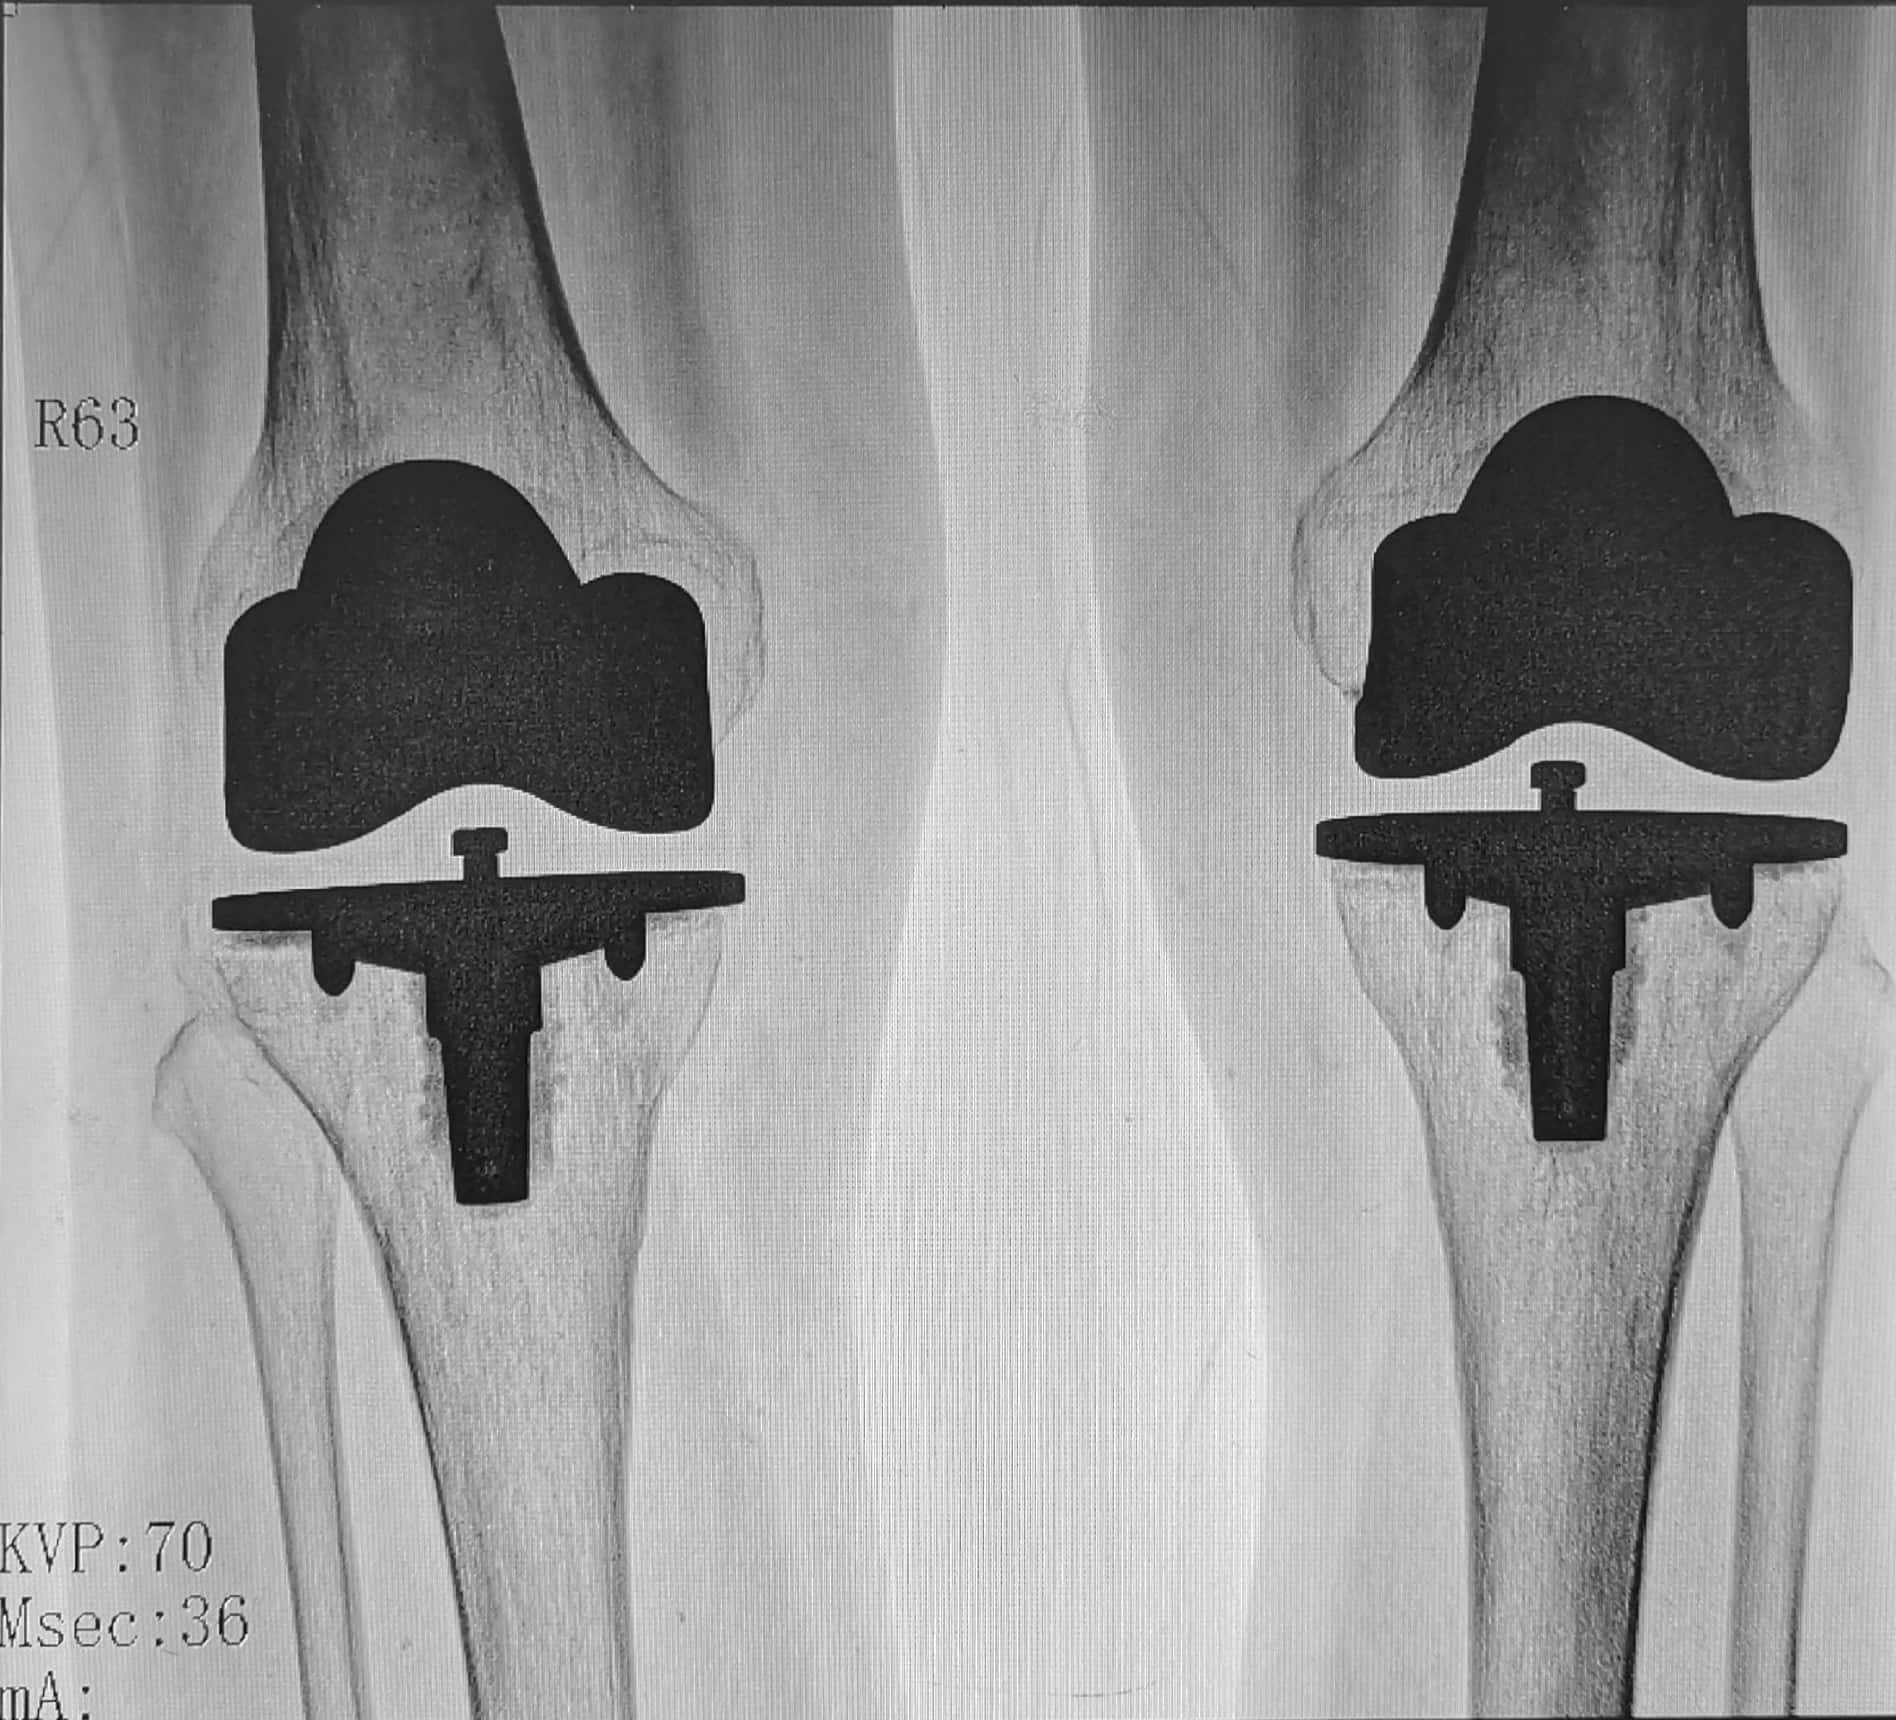

3、人工关节置换术:对于重度膝骨关节炎患者,经保守治疗无效,可考虑接受人工膝关节置换手术。手术目的:①解除严重的关节疼痛;②改善关节功能;③纠正膝关节畸形;④提高生活质量。